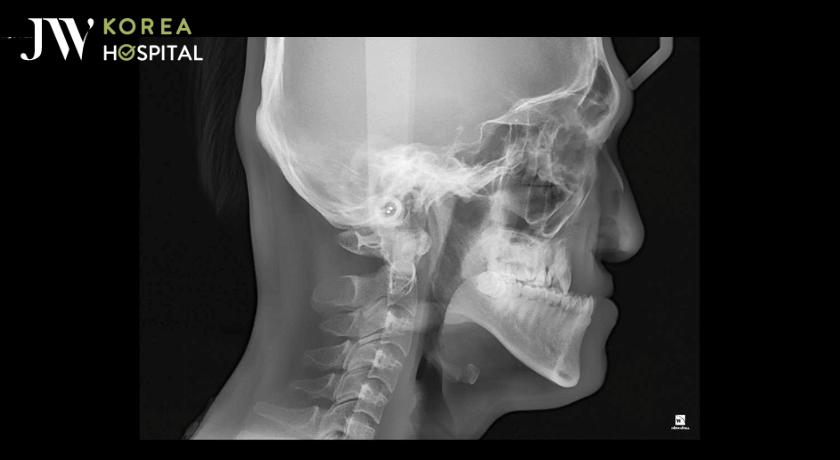

Theo chia sẻ từ ekip bác sĩ JW, ca phẫu thuật hàm móm của anh thuộc dạng khó, bởi cấu trúc xương hàm dưới phát triển quá mức trong khi xương hàm trên lại tụt sâu. Quá trình phẫu thuật kéo dài hơn 6 giờ đồng hồ, yêu cầu độ chính xác cao trong từng thao tác cắt xương, cố định khớp cắn và tái tạo tỷ lệ khuôn mặt.

Hình chụp chẩn đoán mức độ lệch hàm trước khi phẫu thuật